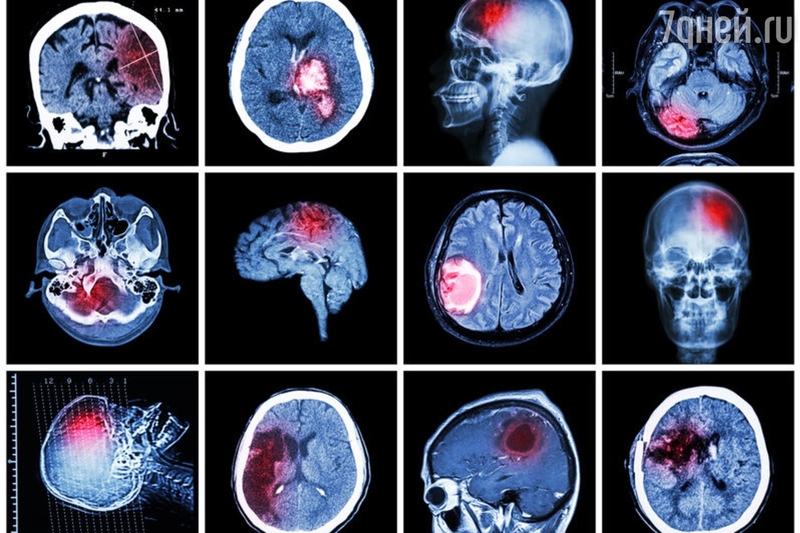

Инсульттун - ишемиялык жана геморрагиялык деген эки түрү кездешет.

- Ишемиялык инсульт – кан тамыр бөгөлүп, (кан уюп), мээге кан жетпей калат.

- Геморрагиялык инсульт – кан тамыр жарылып, мээнин ичине кан куюлат.